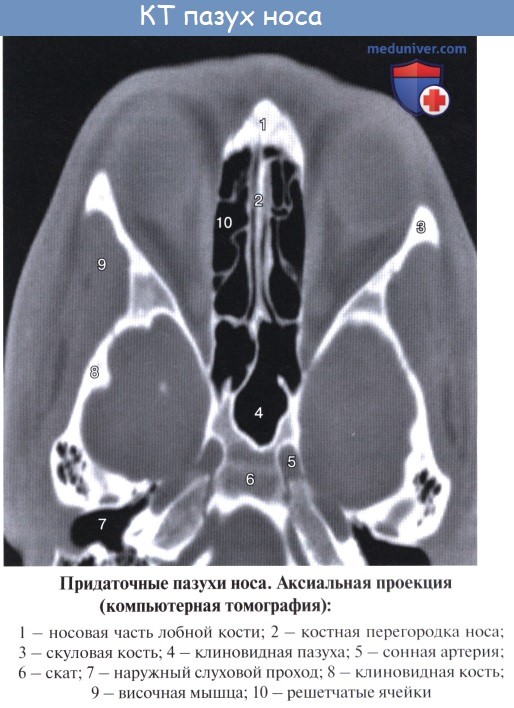

Дополнительным приспособлением для вентиляции воздуха служат околоносовые пазухи, sinus paranasales, также выстланные слизистой оболочкой, являющейся непосредственным продолжением слизистой носа. Это описанные в «Остеологии»:

1) верхнечелюстная (гайморова) пазуха, sinus maxillaris; широкое на скелетированном черепе отверстие гайморовой пазухи закрывается слизистой оболочкой, за исключением небольшой щели;

2) лобная пазуха, sinus frontalis;

3) ячейки решетчатой кости, cellulae ethmoidales, составляющие в целом sinus ethmoidalis;

4) клиновидная пазуха, sinus sphenoidalis.

С каждой стороны к полости носа примыкают верхнечелюстная и лобная пазухи, решетчатый лабиринт и отчасти клиновидная пазуха.

Клиновидная пазуха, sinus sphenoidalis, расположена в теле клиновидной кости непосредственно позади решетчатого лабиринта над хоанами и сводом носоглотки. Сагиттально расположенной перегородкой пазуха делится на две в большинстве случаев неодинаковые по объему части. На передней, наиболее тонкой, стенке в каждой половине пазухи находится отверстие, apertura sinus sphenoidalis. Форма и размеры клиновидной пазухи сильно варьируют. Ее верхняя стенка обращена к передней и средней черепным ямкам.

Средний отдел верхней стенки клиновидной пазухи соответствует турецкому седлу с расположенным в его ямке гипофизом, а кпереди от них — перекресту зрительных нервов.

Снаружи по боковой стенке клиновидной пазухи проходят внутренняя сонная артерия и пещеристый венозный синус. Кроме того, по бокам пазухи проходят глазодвигательный, блоковый и отводящий нервы, прободающие наружную стенку пешеристого синуса, а также I ветвь тройничного нерва.

Нижняя стенка клиновидной пазухи образует свод полости носа.

Решетчатый лабиринт, labyrinthus ethmoidalis, состоит из 2—5 и больше различных по величине и форме решетчатых ячеек, cellulae ethmoidales, которые отграничены от передней черепной ямки орбитальной частью лобной кости и решетчатой костью, а от глазницы — глазничной пластинкой, lamina orbitalis. Сзади клетки решетчатого лабиринта иногда доходят до передней стенки клиновидной пазухи. Клиновидная пластинка решетчатого лабиринта, свободный край которой в полости носа является остовом средней раковины, делит воздухоносные клетки на передние и задние; передние клетки открываются в средний носовой ход, а задние — в верхний.